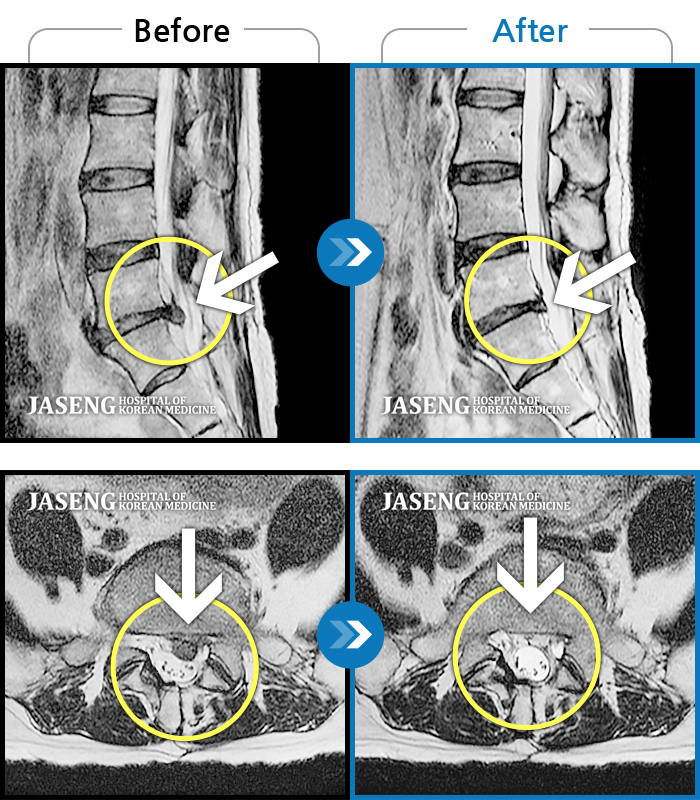

허리디스크

인천 · 강아현 원장

물건을 들다 삐끗한 후 발생한 허리 통증 및 하지 방사통, 하지 감각 저하 및 근력 저하 발생

촬영시기

2025.03.04 ~ 2025.09.10

2025.09.22

조회수 248